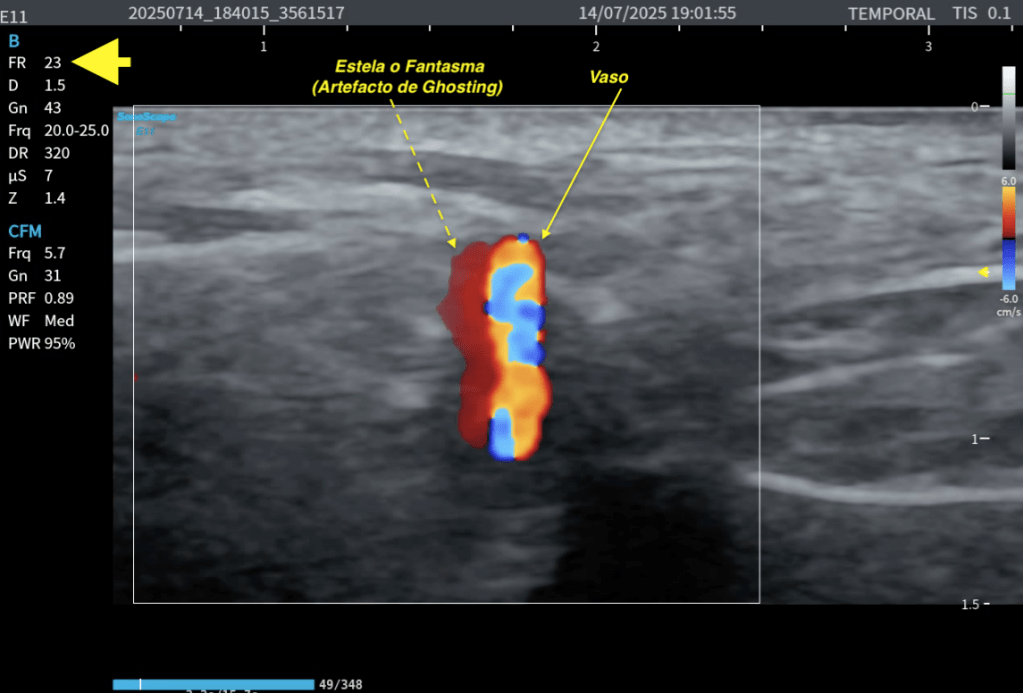

Ghosting

El color no se actualiza a tiempo, queda arrastrado, aparece la imagen fantasma del flujo.

Esto es ghosting Doppler.

El color se “queda” en pantalla, se generan estelas, el ghosting se hace evidente.

El ghosting Doppler se reconoce porque:

El vaso se mueve y el color va detrás, aparecen estelas de color, el flujo parece duplicado, el color se “despega” del vaso al barrer.